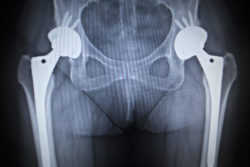

DePuy Orthopaedics is facing a growing multidistrict litigation (MDL), consisting of product liability claims from patients alleging they suffered device complications from a DePuy metal hip implant.

When all metal hip implants were first released, they were thought to be overtly superior to their ceramic or plastic cousins. However, it has recently been discovered that the all metal ball and socket joint components of the device may corrode and shed metal ions when they interact.